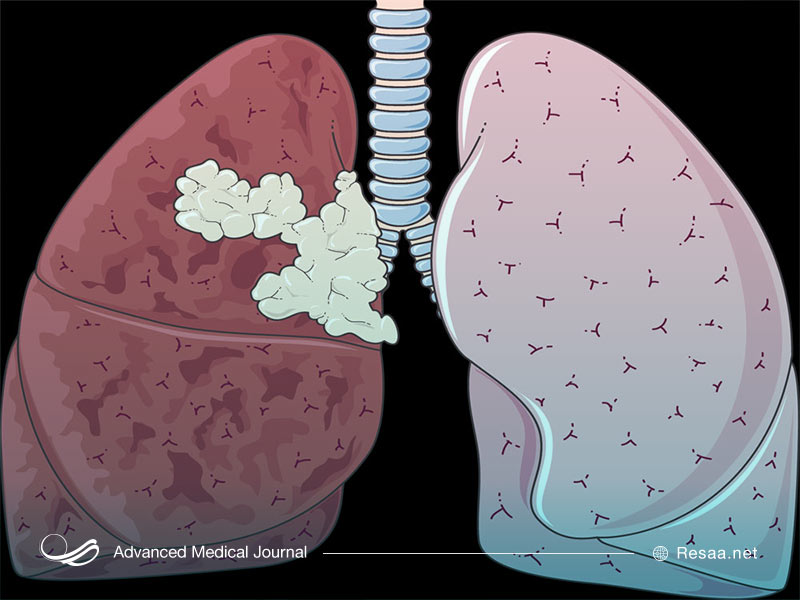

مانند سایر سرطانها، سرطان ریه هنگامی رخ میدهد که فرآیندهای طبیعی تقسیم و رشد سلولی مختل میشود و این باعث توسعه غیرقابل کنترل سلولهای غیرطبیعی میشود. در فرآیند بیماری، سلولها به یک توده یا تومور تبدیل میشوند. هر رشد غیرطبیعی در بدن که مستقیماً به بافتها و اندامها حمله کرده و به قسمتهای دیگر بدن نیز سرایت میکند و حتی با برداشتن تومورها، غدههای جدید رشد میکنند، «سرطان ریه بدخیم» خوانده میشود.

بیشتر سرطانهای ریه در پوشش برونشها (معابر هوایی که از قسمت نای یا لوله تنفسی جدا میشوند) رشد میکنند. سرطان ریه همچنین میتواند در غدد زیرآستر برونشها، غالباً در نواحی بیرون ریهها ایجاد شود. به طور کلی، سرطانهای ریه به دو نوع اصلی بعنی سلول کوچک و سلول غیرکوچک تقسیم میشوند. هر یک از دو سرطان ریه به شیوههای مختلفی رشد میکنند: